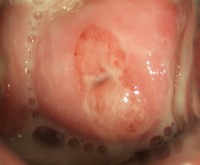

Молочница: симптомы во рту

Молочница ротовой полости – распространенное заболевание в любом возрасте.

У пожилых людей, кандидоз во рту встречается довольно часто. Связано это с использованием протезов. Нередко молочница во рту наблюдается у беременных женщин. На фоне сниженного иммунитета и гормонального сбоя, грибки с легкостью распространяются и паразитируют на слизистой ротовой полости.

Симптоматика кандидоза во рту:

Отек;

- Появление покраснений;

- Чрезмерная сухость ротовой полости;

- Белый налет на слизистой.

При отсутствии лечения, налет становится более явный, образуя консистенцию похожую на хлопья. Появляется боль при глотании, покраснения и заеды в уголках губ, жжение и постоянный зуд в ротовой полости.

Диагностируется заболевание при визуальном осмотре. В качестве подтверждения диагноза, врач направит сдать анализ – биоматериалом выступает в данном случае налет, который легко отделяется.